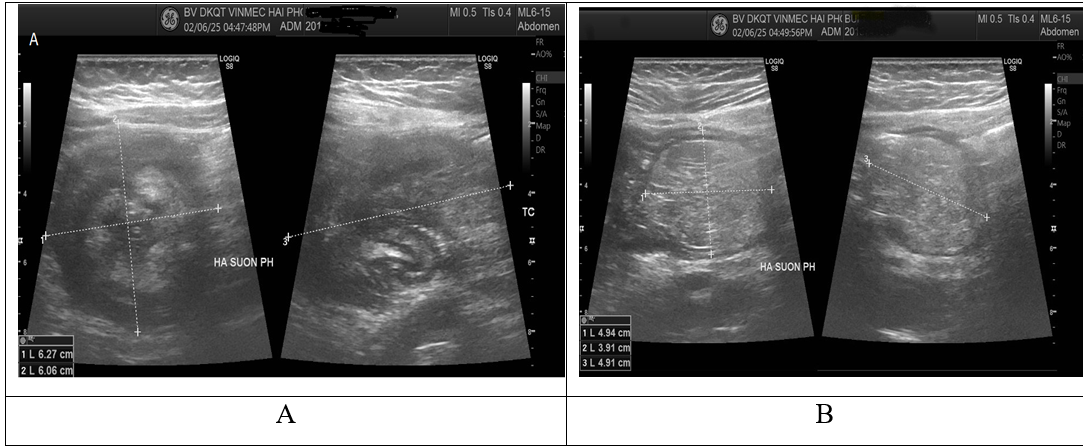

Một bệnh nhân nữ 48 tuổi, khám ở khoa ngoại tổng quát với các triệu chứng đau bụng kéo dài khoảng 2 tuần và trở nặng hơn trong 2 ngày gần đây. Đau bụng âm ỉ có lúc trội thành cơn ở vùng thượng vị và hạ sườn phải, đặc biệt là hạ sườn bên phải kèm theo đi ngoài phân lỏng. Ngoài đau bụng, không có bất kỳ triệu chứng đáng kể nào khác (buồn nôn, nôn, tiểu khó, v.v.). Khám cho thấy huyết áp, mạch và nhiệt độ cơ thể bình thường, bụng chướng nhẹ. Có cảm giác đau ở hạ sườn phải, tuy nhiên, không có phản ứng dội và âm thanh ruột bình thường. Khám tim và phổi không phát hiện bất thường. Số lượng bạch cầu (8.4G/L), hemoglobin, chỉ số hematocrit, CRP (6.52mg/L) và tất cả các thông số sinh hóa khác đều nằm trong giới hạn bình thường. Siêu âm ổ bụng cho thấy hình ảnh khối lồng ruột ở góc hạ sườn phải và một khối tăng âm ở cạnh khối lồng có liên quan đến đoạn này ở giữa ổ bụng nghĩ đến khối u mỡ (Hình 1). Sau khi phát hiện ra điều này, đã đề nghị tiến hành chụp cắt lớp vi tính có cản quang tĩnh mạch. Quan sát thấy khối lồng ở vùng bụng trên bằng chụp CLVT thấy đại tràng lên chui vào đại tràng ngang. Vị trí lồng ruột phát hiện có một khối tỷ trọng mỡ, kích thước đo được là 40x53x55 mm (Hình 2). Với chẩn đoán lồng ruột đại tràng do khối u mỡ, bệnh nhân đã được phẫu thuật cấp cứu. Không có dịch tự do trong khoang bụng trong quá trình phẫu thuật. Phát hiện khối lồng ruột đại tràng ở đại tràng ngang và lòng đại tràng bị hẹp nhiều. Tiến hành gỡ khối lồng ruột và tìm nguyên nhân lồng, nhưng không được. Với tổn thương này, phẫu thuật viên đã cắt bỏ một nửa đại tràng phải và nối hồi – đại tràng.(Hình 3). Trong mô tả của giải phẫu bệnh: đoạn đại tràng đã cắt bỏ, tổn thương được chẩn đoán là u mỡ dưới niêm mạc đại tràng. Không phát hiện bất kỳ bệnh lý nào khác qua quan sát và thăm khám ở các cơ quan khác trong ổ bụng trong trường phẫu thuật.

Hình 1. Hình ảnh siêu âm:

(A) Khối lồng ruột vùng hạ sườn phải

(B): khối tăng âm nằm cạnh khối lồng ruột nghĩ đến khối u mỡ

Siêu âm bụng tổng quát có thể phát hiện ra tổn thương lồng ruột và có khối tăng âm mà không có mạch máu bên trong [ 10 ]. Trong trường hợp của chúng tôi, khối u mỡ được phát hiện là tổn thương tăng âm khi đánh giá siêu âm và có hình ảnh khối lồng ruột. Chụp cắt lớp vi tính (CLVT) là công cụ chẩn đoán phổ biến nhất với độ nhạy 71%–87% và độ đặc hiệu lên đến 100% để phát hiện lồng ruột [1]. Chụp cắt lớp vi tính cho thấy khối u ranh giới rõ và mật độ mỡ đồng nhất điển hình (-40 đến -120 đơn vị Hounsfield) [ 6], [7], [10]. Trong trường hợp của chúng tôi, chụp CLVT cho thấy ngoài khối lồng ruột còn có u mỡ có cùng mật độ với mô mỡ (- 83 đơn vị Hounsfield). Tuy nhiên, việc xác định điểm dẫn bệnh lý đặt ra một thách thức. Chụp cộng hưởng từ (MRI), nội soi đại tràng và chụp bari được sử dụng để tìm nguyên nhân của lồng ruột đại tràng và hơn 70% bệnh nhân đã trải qua hai hoặc nhiều đánh giá để tìm nguyên nhân của lồng ruột đại tràng do u mỡ gây ra [1].